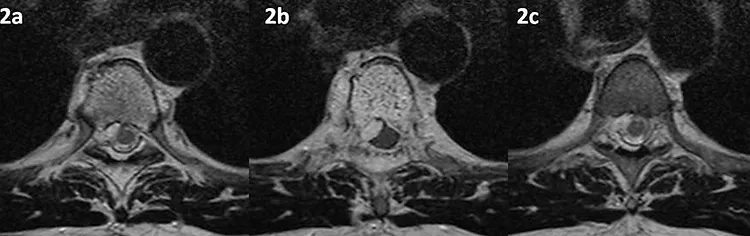

Figura 2 (a-c): Imagens consecutivas de RM da coluna torácica no plano transversal na ponderação T2.

Figura 2 (a-c)’: Imagens consecutivas de RM da coluna torácica no plano transversal na ponderação T2 mostrando o corpo vertebral D5 com típico aspecto pontilhado (seta larga branca em 2b’) e o tecido no espaço epidural comprimindo o saco dural (setas vermelhas). Há também tecido semelhante nas partes moles paravertebrais (setas azuis). Note que na figura 2a’ é possível identificar a medula espinhal (seta rosa) e o canal raquiano com o alto sinal do líquor (seta laranja). Já na figura 2b’ não é possível identificar o líquor ao redor da medula espinhal comprimida (seta rosa), observado apenas em imagem mais inferior (2c’).